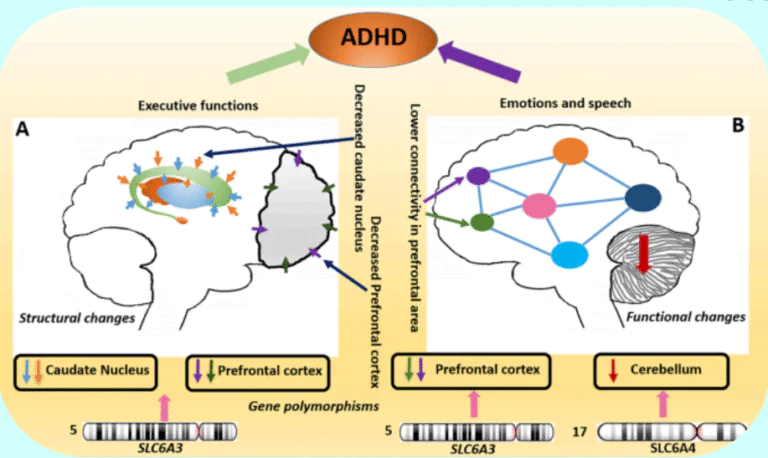

ATTENTION DEFICIT HYPERACTIVITY DISORDER (ADHD)

“Focused support helps build focused minds.”

Definition

ADHD is a neurodevelopmental disorder characterised by inattention, hyperactivity, and impulsivity. It affects children and may continue into adulthood.

Common Symptoms

- Difficulty concentrating

- Hyperactivity

- Impulsive behavior

- Poor academic performance

How Stem Cell Therapy May Help

Stem cell therapy may support neural balance and improve attention pathways. It is considered supportive and combined with behavioral therapy and structured educational support.

ATTENTION DEFICIT HYPERACTIVITY DISORDER (ADHD)

“Focused support helps build focused minds.”

Definition

ADHD is a neurodevelopmental disorder characterised by inattention, hyperactivity and impulsivity. It affects children and may continue into adulthood.

Common Symptoms

- Difficulty concentrating

- Hyperactivity

- Impulsive behavior

- Poor academic performance

Diagnostic Tests

- Behavioral assessment

- Attention scoring scales

- Psychological evaluation

- Blood screening

How Stem Cell Therapy May Help

Stem cell therapy may support neural balance and improve attention pathways. It is considered supportive and combined with behavioral therapy and structured educational support.